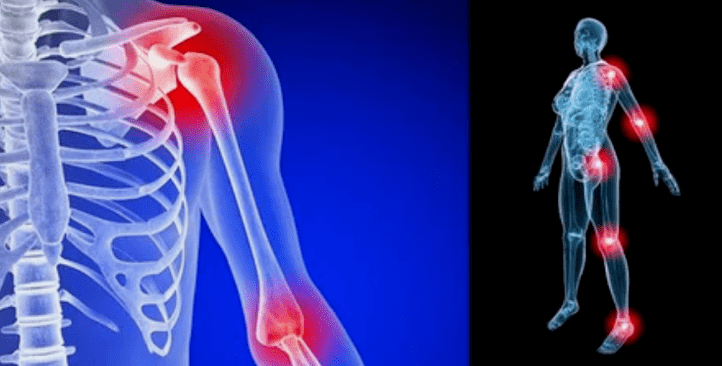

The manifestations of the disease vary by location, and these signs are often reflected in the knees, shoulders, and hips due to high loads.

- pain.They are very low in the initial stages and the intensification of sensation is exacerbated.Initially, until you wake up, the joints will be injured and the feeling will disappear.As time goes by, the pain occurs at night, after prolonged walking, running, etc.In the final stage, pain syndrome has been chasing a person.

- Redness.It is located near the diseased joint, which indicates the inflammatory process and progression of the disease.Doctors know that the synovial shell is affected, which can cause fluid accumulation and increased pain.